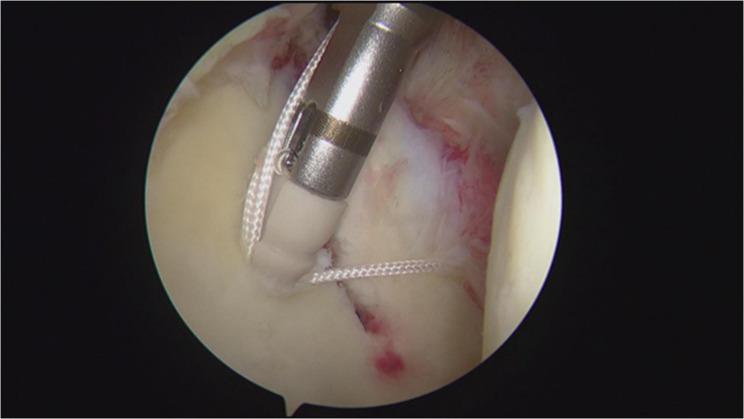

Compared to patients who underwent continuous controlled hypotension throughout rotator cuff repair, those who received controlled hypotension only during critical surgical steps-specifically stapling (Fig. 1) and suture knotting (Fig. 2)-experienced higher-quality postoperative awakening and fewer complications.

与在整个肩袖修复过程中持续进行控制性低血压的患者相比,仅在关键手术步骤(具体为钉合(图1)和缝合打结(图2))期间接受控制性低血压的患者术后苏醒质量更高,并发症更少。